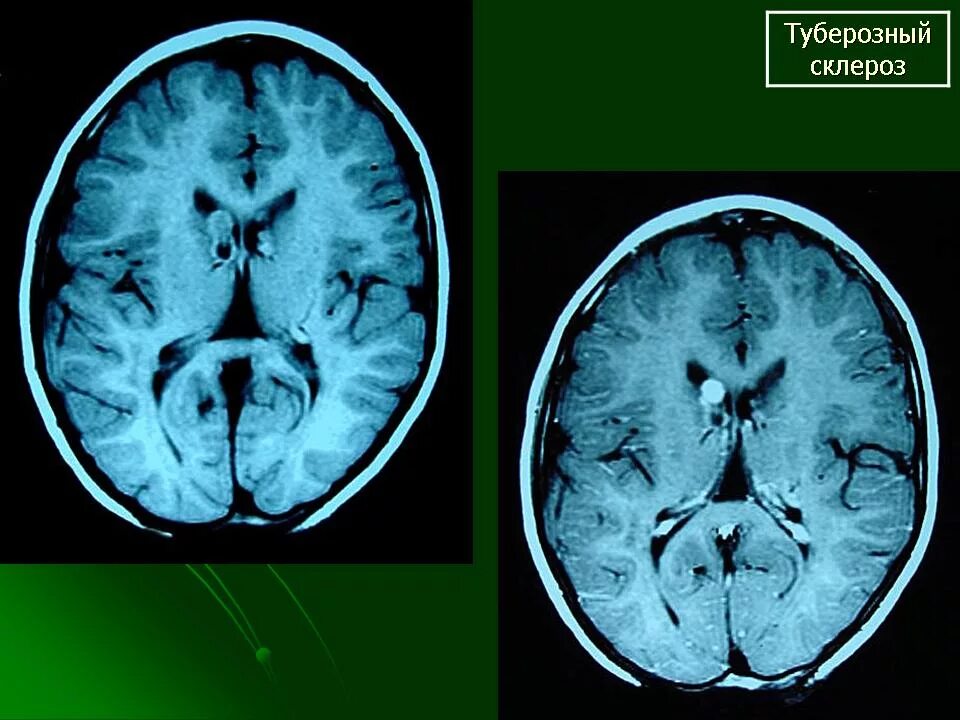

Туберкулезный склероз